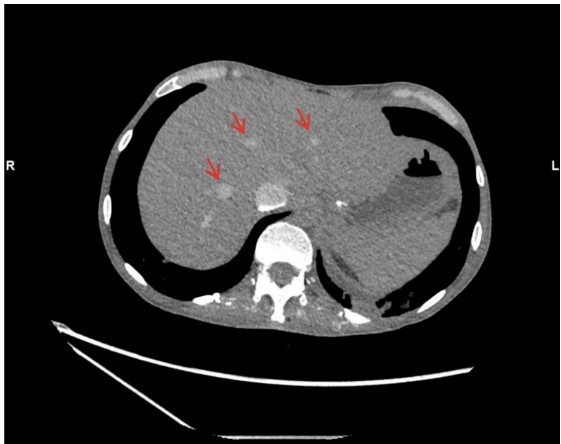

However, the acquisition revealed persistently poor opacification of the pulmonary trunk throughout the imaging interval (Fig. 1). The axial slices demonstrated pathognomonic features of circulatory collapse including dependent layering of contrast within the right ventricle, contrast pooling within inferior vena cava (IVC) and absence of contrast with in the left ventricle and aorta, indicating lack of forward flow (Fig. 2). Due to these highly suspicious findings, the examination was extended to the abdomen, which confirmed pooling of contrast within the hepatic veins (Fig. 3).

The presence of these radiological markers provided definitive evidence that a "silent" cardiac arrest had occurred prior to the contrast injection. Upon recognizing these features, our team immediately transitioned from diagnostic imaging to active resuscitation. Although we achieved the return of spontaneous circulation (ROSC), the patient succumbed to his illness three days later in the intensive care unit.

The hallmark findings in this case were dependent contrast pooling and layering with in the inferior vena cava, hepatic veins, and right heart chambers, accompanied by absent opacification of the pulmonary arteries and left heart. These features reflect a total cessation of effective cardiac output. In the absence of forward flow, the high-density contrast medium (which is heavier than blood) leading to gravitational sedimentation of contrast in the most dependent venous structures. This phenomenon is further characterized by the absence of contrast opacification in the pulmonary arteries and left- sided cardiac structures. The additional observation of contrast stasis in the right heart further underscores the severity of circulatory arrest.